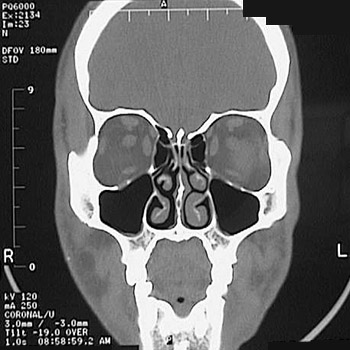

This is a normal sinus CT scan demonstrating the orbit and ethmoid sinus and nasal cavity and concha and maxillary sinus and maxilla in the anterior skull.